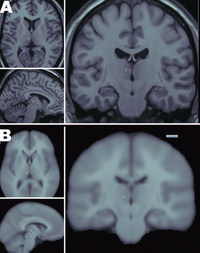

Hjernens cortex opdeles i Gyri og Sulci, hvor ca. 70% af cortex er lokaliseret i sulci, altså ikke umiddelbart synlig når man kigger på hjernens overflade. Lokalisering og udformning af sulci er ganske variable på nær enkelte sulci (lateral fissuren, Fissura interhemispherica, Sulcus Centralis, Sulcus Cinguli og Sulcus Parietooccipitalis) dette ses fint illustreret i Fig.1 hvor der er lavet fusion af MR-skanninger fra 452 hjerner. Man kan se af de fleste sulci og gyri bliver "midlet ud" fordi de har variable lokalisation, mens nogle enkelte tydeligt træder frem, fordi de har en relativt konstant placering. I dybet af lateral fissuren mellem frontallappen og temporallappen er Insula, lokaliseret. De tilstødende dele af frontal- og temporallen på hjernens konveksitet kaldes henholdsvis frontal og temporal operculum, hvor operculum betyder læbe.